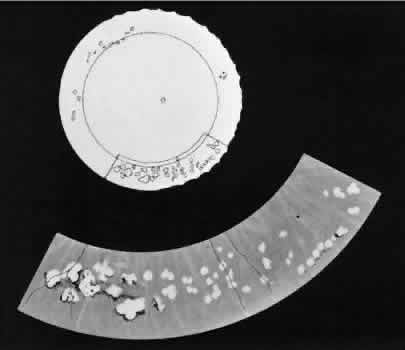

chorioretinal lesions.  Fig. 24. Paving-stone degeneration. Note multiple round foci of depigmentation in

temporal sector. Larger lesions show scalloped margins and linear pigmentation

resulting from confluence of several smaller lesions. (× 65.) Fig. 24. Paving-stone degeneration. Note multiple round foci of depigmentation in

temporal sector. Larger lesions show scalloped margins and linear pigmentation

resulting from confluence of several smaller lesions. (× 65.)